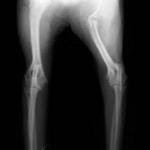

症例:柴犬 3歳

左後肢の完全挙上を主訴に来院されました。触診にて近位足根関節の過伸展を、レントゲン検査にて左足根関節周囲の軟部組織の腫脹、ストレス撮影によって距骨・踵骨と第4足根骨・中心足根骨間の脱臼および過伸展を認めました。

術前正面像左関節の腫れ

左足根関節の軟部組織が腫脹しています。

術前正面像

術前側面像屈曲位

術前側面像伸展位